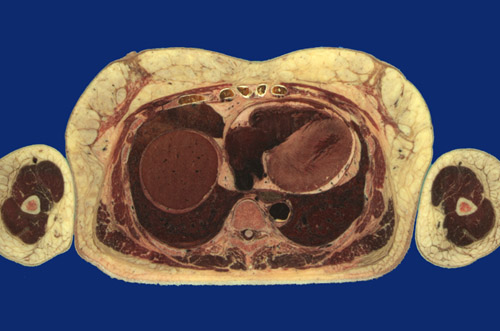

Identify the following regions in the image above: Latissimus dorsi - Serratus anterior - External oblique - Rectus abdominis - Sacrospinalis - Sternum - Breast - Liver, right lobe - Left lower lobe - Right lower lobe - Esophagus - Descending aorta - Vertebral body - Spinal cord